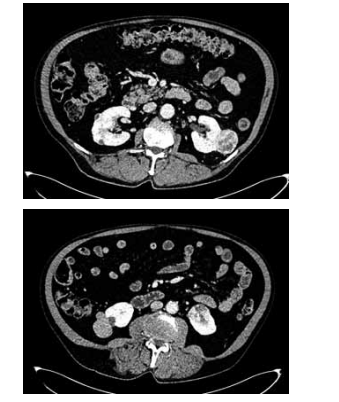

Homem de 65 anos refere hematúria macroscópica há

1 mês. Nega comorbidades ou cirurgias prévias e tem

antecedente de cálculos urinários. É tabagista há 40

anos, de um maço por dia. Foi solicitada a tomografia de

abdome e pelve, demonstrada a seguir:

(Arquivo pessoal; imagem usada com autorização)

Com essas informações, qual o diagnóstico, uma possível complicação pós-operatória e a medida necessária para reduzir o risco dessa complicação, respectivamente?